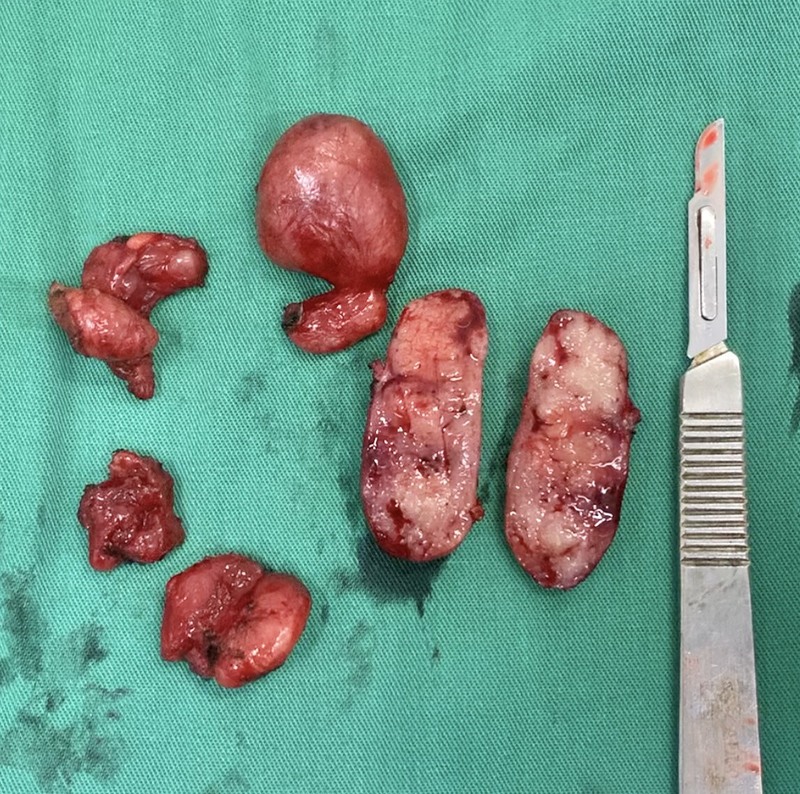

VIII. ĐẠI THỂ

- Bề mặt cắt có màu hồng nâu đồng nhất

- Không có biểu hiện xuất huyết hoặc hoại tử

- Bệnh nhân được phẫu thuật nạo hạch

- Kết quả giải phẫu bệnh: hạch tăng sản nang